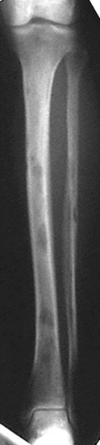

How mineralised does bone have to be to be seen on an X-Ray?

50%

Describe the pathology of osteoporosis.

Imbalance in bone remodelling so more resorption than formation. Affects trabecular bone as it is more metabolically active.

Holes where the trabecular bone has been resorbed away and remaining trabecular bone is thinner and less interconnected

Cortical bone will become thin too -> compression fractures of spine, long impact fragility fractures in long bones.